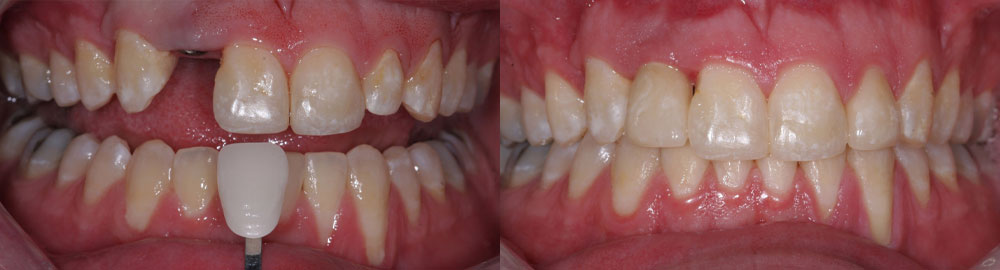

- Natural Appearance: Dental implants blend seamlessly with your natural teeth, providing a lifelike restoration that enhances your smile.

- Final Restoration: Once the implants have fully healed and integrated with the jawbone, custom-made dental crowns, bridges, or dentures are securely attached to the implants, completing your smile restoration.